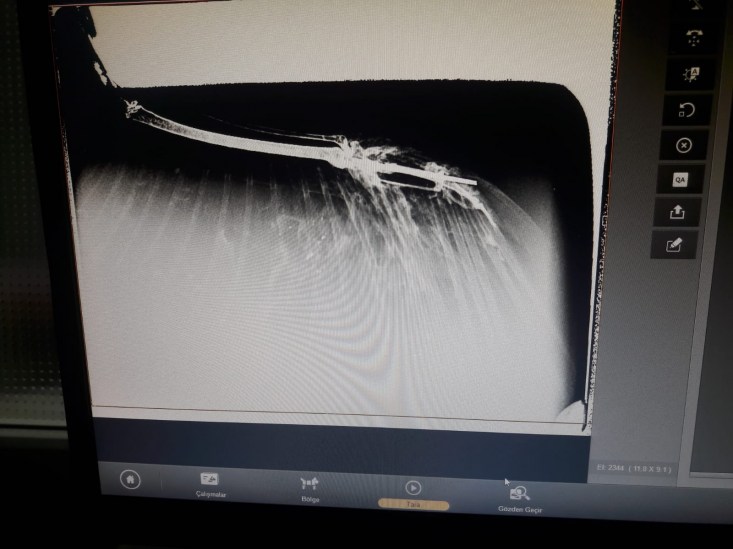

yapılmak üzere ERVET veteriner hekimliğine getirildi. Saçmalardan dolayı

kanatlarında ve kemiklerde kırılmalar meydana gelen Doğan kuşları çekilen

röntgenin ardından tedavilerine başlandı.

tarafından getirildi bu kuşumuz. Önce röntgenini çektik. Röntgeninde kemiğinin

saçma ile parçalandığını, darmadağınına yakın bir parçalanma yaşamış kemiği.

Pazar günü bunu operasyona aldık. Kırık kemiğinin parçalarını düzelttik. Kalan

kemiklerin arasındaki bağlantıyı sağladık. Önce tabi şoka giriyorlar bu durum